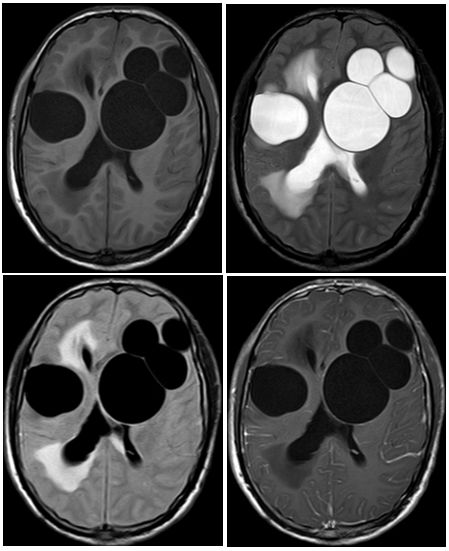

病例4

患者,12岁,反复癫痫发作,头MRI如下:

答案:大脑多结节和空泡状神经元肿瘤( MVNT )

MVNT是一种良性浅表性神经元瘤,多表现为长期的癫痫发作。该肿瘤2013年被首次报道。临床上,MVNT多为偶然发现,患者多表现为长期的癫痫发作。这个病例好多老师不认识,其影像特点是MRI表现为皮层下小团簇状、囊性、结节性病变,T2/FLAIR呈高信号(像很多泡泡)(T1可呈略低信号)。病变多位于深部皮层带和浅表皮层下白质,多无明显强化,可有点状轻度强化,无扩散受限及磁敏感效应。病变很少进展或体积变大,多无占位效应及瘤周水肿。故该病多建议进行观察随访,不建议进行干预。鉴别诊断有局灶性皮质发育不良、瘤样血管间隙、胚胎发育不良性神经上皮肿瘤(DNET)、毛细胞性星形细胞瘤、节细胞胶质瘤、多形性黄色星形细胞瘤等。容易误诊为DNET,DNET为边界清楚、楔形囊泡状皮质内肿块,常伴有皮质发育不良。DNET也多见于年轻患者,生长也非常缓慢,表现为难治性癫痫发作。颞叶(常常是杏仁核和海马区)是最常见的发病部位,其次为额叶,多呈边界清楚的三角形。